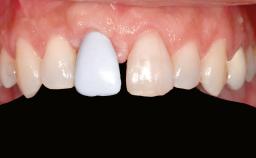

Iliac and Calvarial Bone Blocks for Onlay Grafting of a Severely Resorbed Edentulous Maxilla

| Provisional Implant-Supported Prosthesis | Prosthodontic margin < 3 mm apical to mucosal crest Prosthodontic margin < 3 mm apical to mucosal crest |